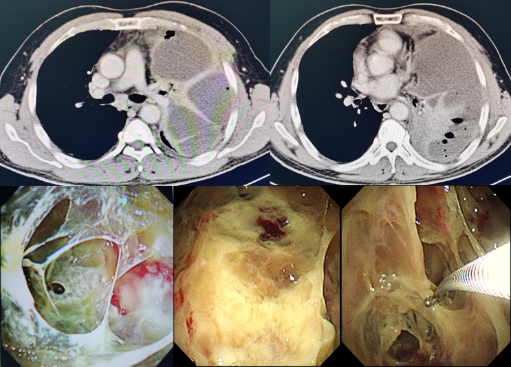

图2. 胸膜腔感染:脓胸患者的胸部CT及胸腔镜下表现,镜下清理脓腔